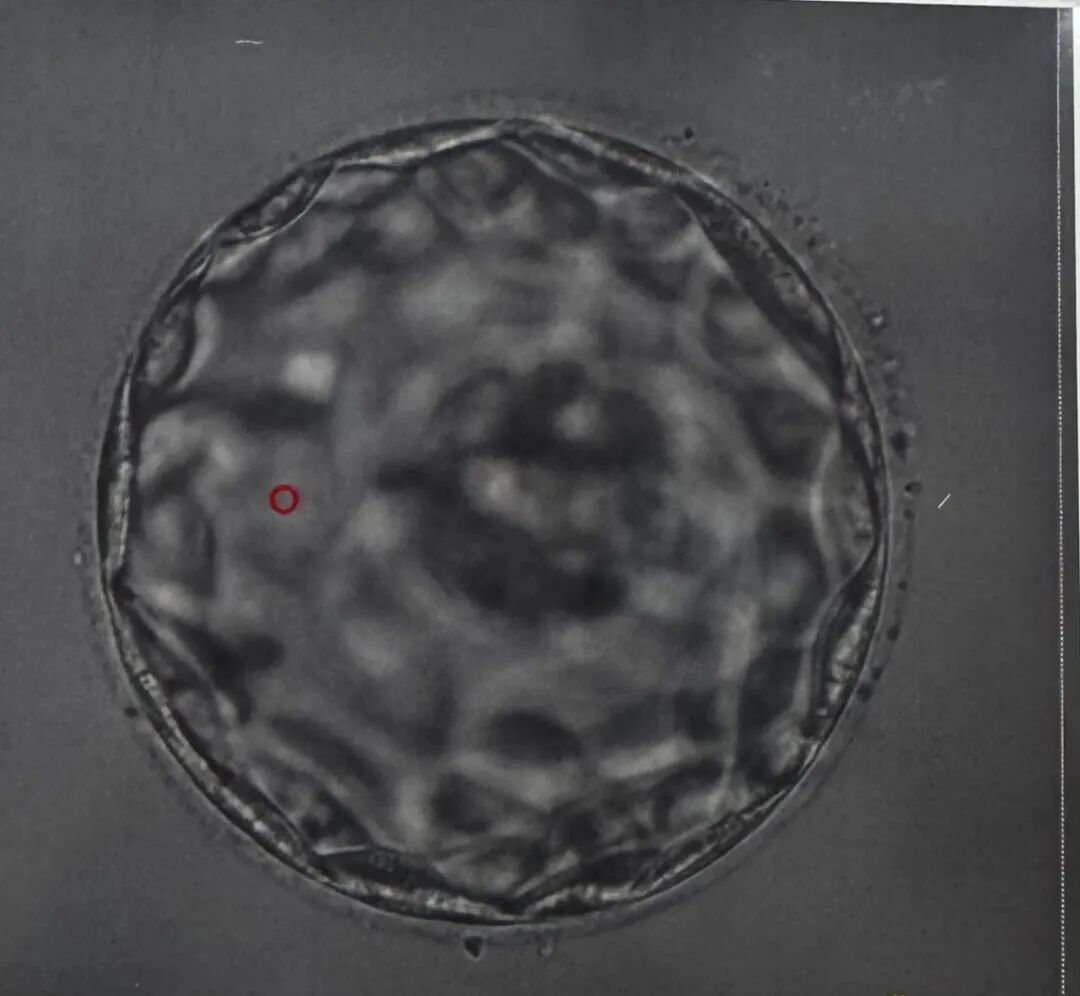

这一次的宝宝,是准妈妈梦寐以求的小王子。在胚胎移植前,准父母特别选择了在美国应用广泛的PGT(胚胎植入前遗传学筛查)技术,对胚胎进行了全面的染色体筛查。这项技术不仅显著降低了遗传疾病的发生风险,也在法律允许范围内进行了性别筛选,实现了XY优选。于是这个被期待已久的男宝宝,如愿而至!我们也满心期待着,迎接他闪亮登场的那一天!